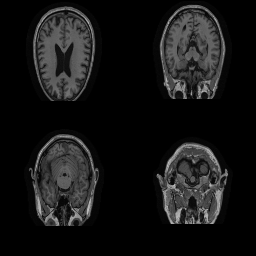

| Original | Renderings after de-identification | Original | MRI slices after de-identification | ||||||

| CP-GAN | FACE MASK | DEFACE | QUICKSHEAR | CP-GAN | FACE MASK | DEFACE | QUICKSHEAR | ||

Benchmark De-Identification Methods. We compare our result with three publicly available and widely-established methods for de-identification of MRI head scans, depicted in Figure 3. All methods have in common that they (1) are not deep-learning-driven, (2) require no additional training and (3), are used on a day-to-day basis in neuroscience and clinical research. All procedures were applied with default settings on images of resolution . The methods include QUICKSHEAR [Schimke et al.(2011)Schimke, Kuehler, and Hale], FACE MASK [Milchenko and Marcus(2013)], and DEFACE [Bischoff-Grethe et al.(2007)Bischoff-Grethe, Ozyurt, Busa, Quinn, Fennema-Notestine, Clark, Morris, Bondi, Jernigan, Dale, Brown, and Fischl]. Descriptions of the methods are provided in the Appendix. We also include MRI WATERSHED [Ségonne et al.(2004)Ségonne, Dale, Busa, Glessner, Salat, Hahn, and Fischl], a skull-stripping method that removes everything except the brain.